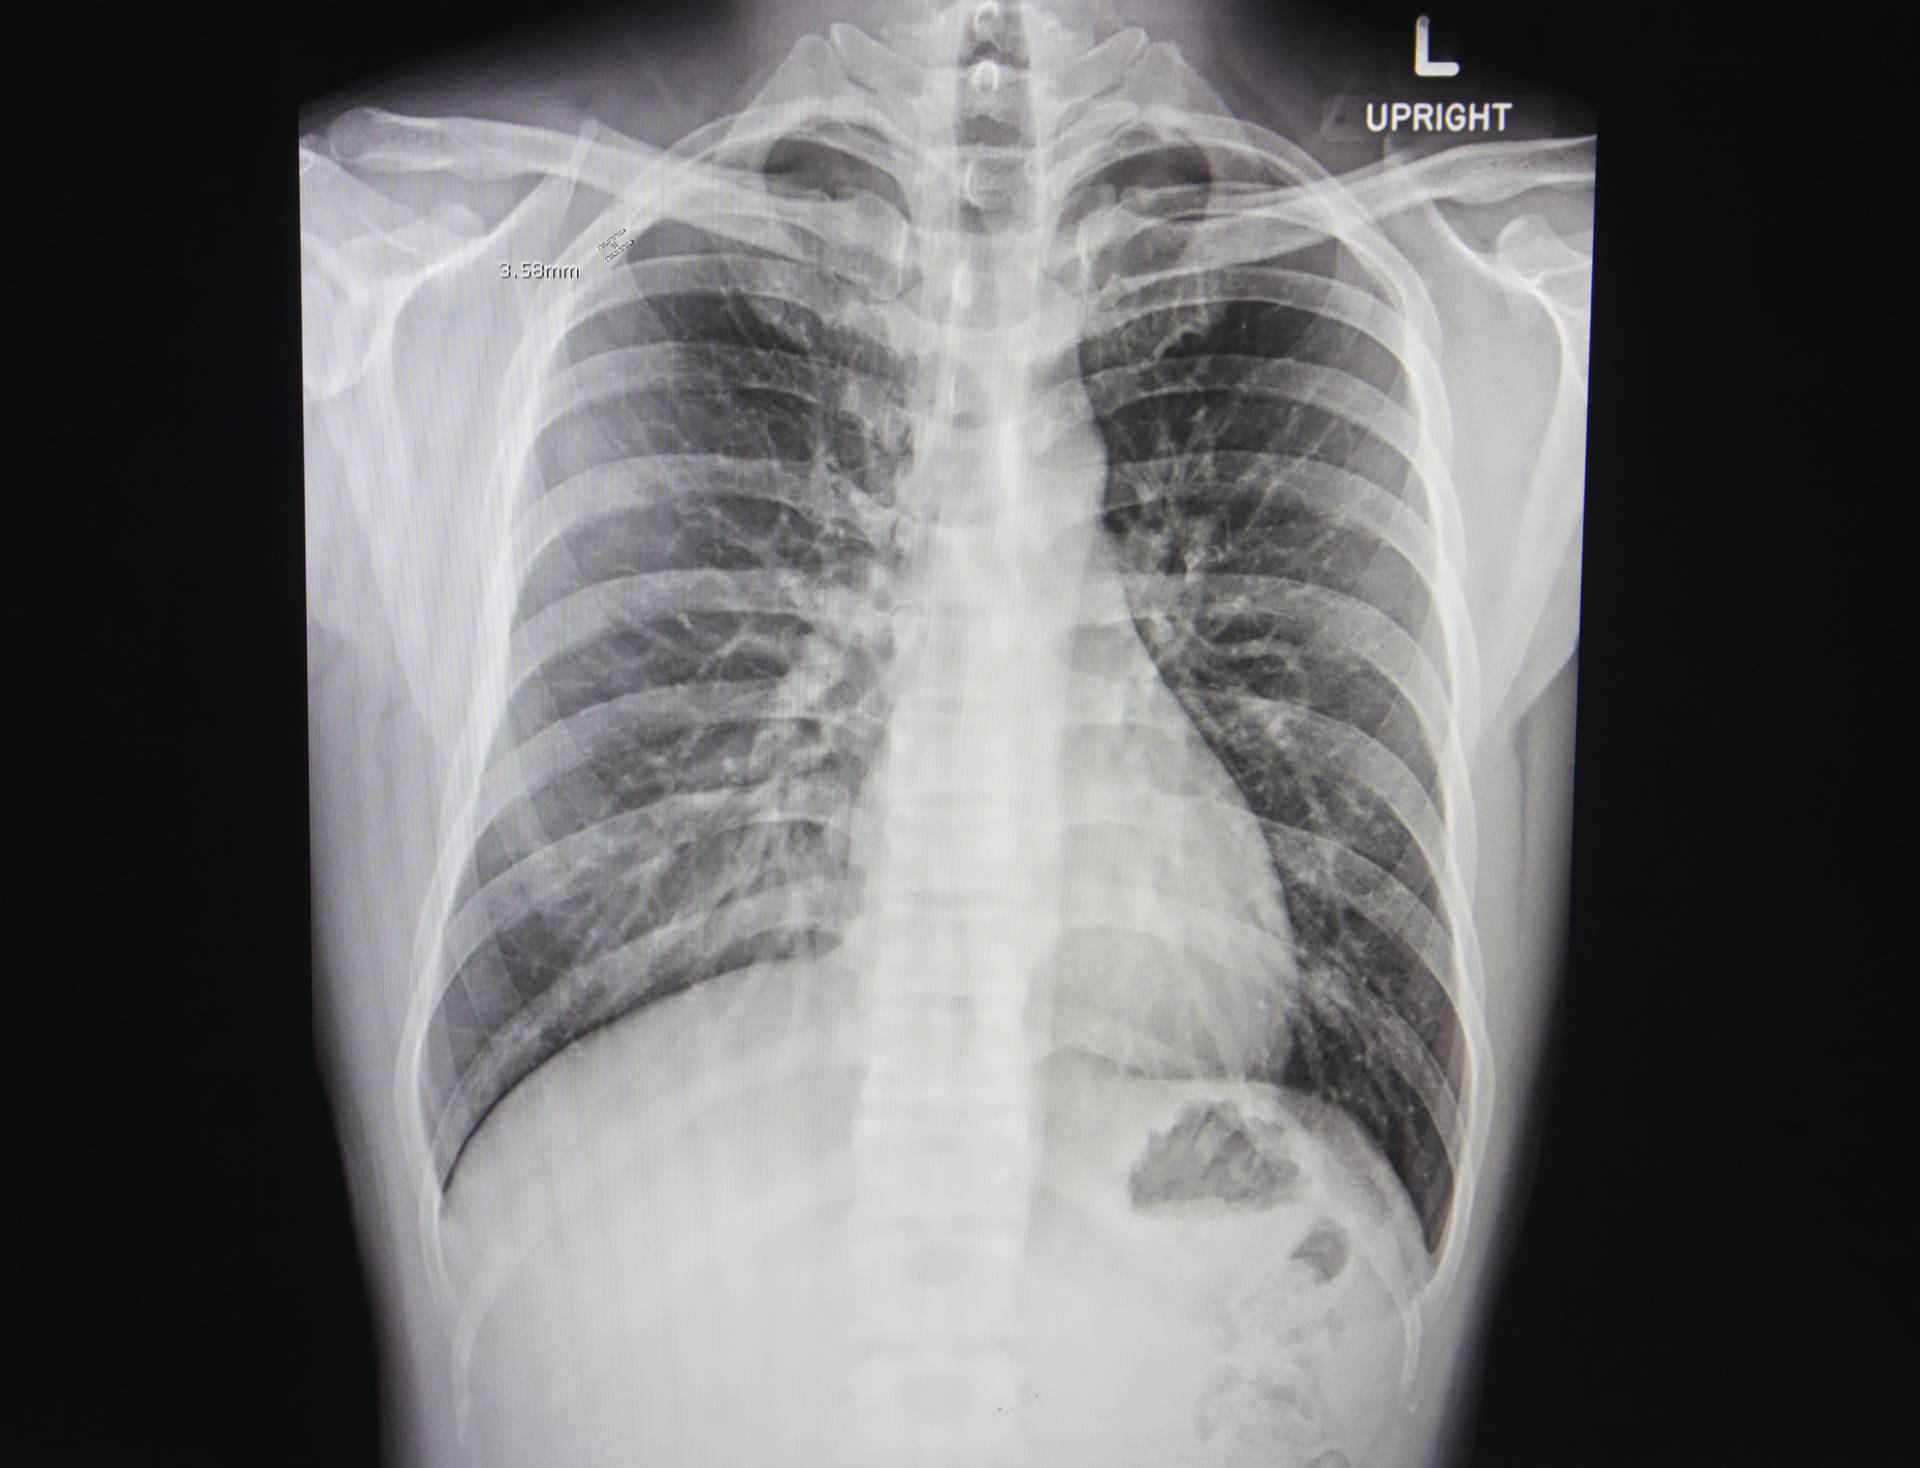

qXR, deep learning AI software swiftly analyses Chest X-rays to triage scans for patients with lung cancer suspicion, enhancing efficiency and shortening time to diagnosis

Lung cancer is the biggest cause of cancer deaths in the UK. 5-year survival rate is poor at just 14.6% and 30% of patients die within 90 days of diagnosis, with around 48,600 new cases and 35,300 deaths annually. The National Optimal Lung cancer Pathway (NOLCP) recommends rapid progression from chest X-ray (CXR) to computerised tomography (CT) scan to reduce time to diagnosis for Lung cancer patients. However, radiology capacity and increasing workload hinders implementation of NOLCP, with the current average time at 63 days. Recently published work found that immediate radiographer CXR reporting and triage straight to CT significantly reduced time to diagnosis of Lung cancer by almost half from a median of 32 days compared to routine CXR reporting. Using qXR, an Artificial Intelligence (AI) solution for immediate CXR reporting should have a similar impact on time to diagnosis.

qXR is AI-powered X-ray software which will be utilised for triaging CXRs immediately after they have been captured. This triage should allow for quicker and more accurate reporting. The project investigates the impact of AI triage of CXRs against routine non-triaged reporting on time to CT and final diagnosis of a patient. The triage alert could lead to faster reporting of suspicious X-rays reducing the wait time for CT appointments. qXR double-read also enhances accuracy of reporting, potentially improving lung cancer detection. The project tests AI CXR triage using qXR across NHS sites, assessing clinical effectiveness, economic viability, and integration. Data collection measures impact on Lung cancer diagnosis time, influencing NOLCP implementation.